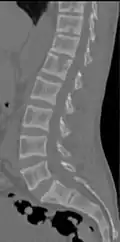

CT scan of the same case.[18]

Renal osteodystrophy is usually diagnosed after treatment for end-stage kidney disease begins; however the CKD-MBD starts early in the course of CKD.[1][6] In advanced stages, blood tests will indicate decreased calcium and calcitriol (vitamin D) and increased phosphate, and parathyroid hormone levels. In earlier stages, serum calcium, phosphate levels are normal at the expense of high parathyroid hormone and fibroblast growth factor-23 levels. X-rays will also show bone features of renal osteodystrophy (subperiostic bone resorption, chondrocalcinosis at the knees and pubic symphysis, osteopenia and bone fractures) but may be difficult to differentiate from other conditions. Since the diagnosis of these bone abnormalities cannot be obtained correctly by clinical, biochemical, and imaging methods (including measurement of bone-mineral density), bone biopsy has been, and still remains, the gold standard analysis for assessing the exact type of renal osteodystrophy.[6][16]